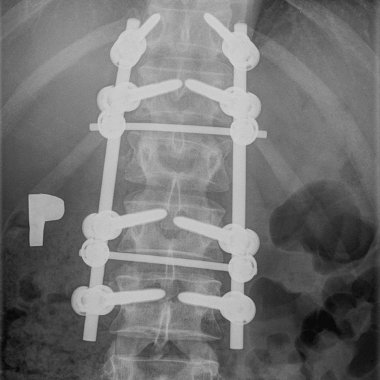

- stabilizacje transpedicularne i implanty międzytrzonowe PLIF Plivios ,

- stabilizacja kręgosłupa lędźwiowo-krzyżowo-biodrowa,

- stabilizacja transpedicularna przy złamaniu kręgosłupa lędźwiowego,

- stabilizacja kręgosłupa z wykorzystaniem śrub kaniulowanych,